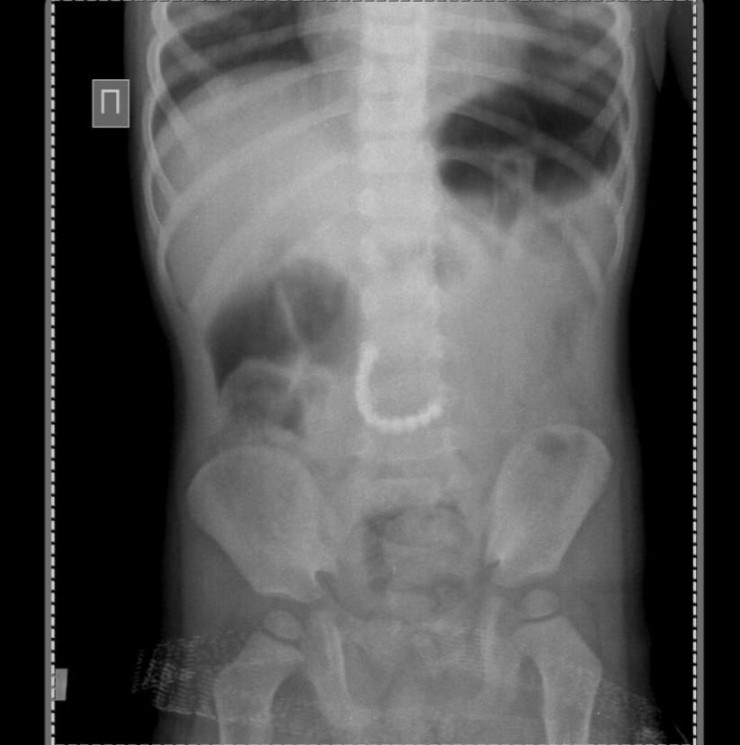

Ребенок поступил в областную детскую больницу в экстренном порядке 4 февраля. У него были сильные боли в животе, его неоднократно рвало. Рентгенография органов брюшной полости показала наличие в ней инородных тел.

"В экстренном порядке проведена сложная операция, в ходе которой обнаружено повреждение (перфорация- прим.) тощей кишки. Из желудочно-кишечного тракта малыша удалось извлечь магнитные детали от детских игрушек в количестве 11 штук. Именно они и повредили кишку и склеились между собой", — рассказал заместитель директора по хирургической службе областной детской клинической больницы Жанат Елубаев.